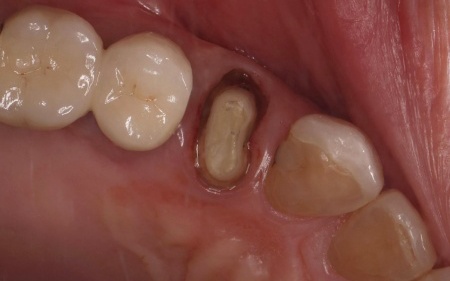

60代男性 歯に合わなくなった被せ物をジルコニアクラウンに交換した症例

拝見したところ、右上4番目の歯には白い被せ物が入っていましたが、加齢により歯ぐきが下がったことで被せ物が合わなくなり、土台が見えて黒くなっていました。

この歯は笑ったときに見えやすい部分のため審美性に影響が出ており、さらにこのまま放置すると隙間から細菌が入り込んで虫歯が再発するリスクもあります。

以上のことから、被せ物を取り外し新しい被せ物に交換する必要があると診断しました。

まず古い被せ物を除去して土台の形を整え、精密な型取りを行いました。